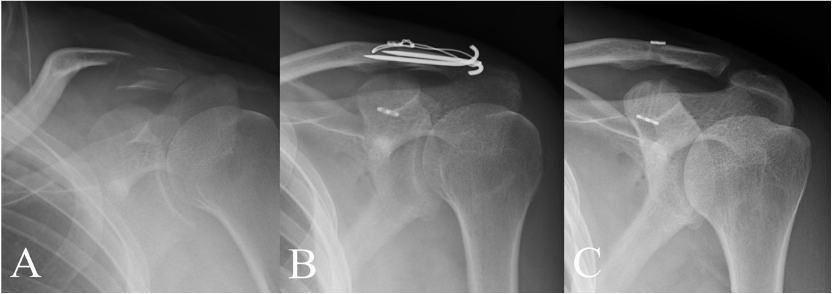

铆钉结合张力带克氏针固定